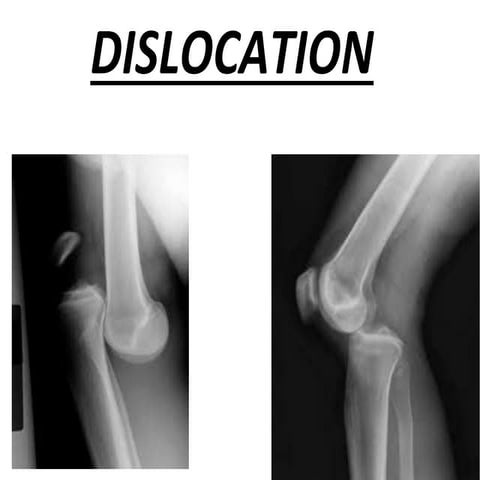

Types

Anterior dislocation-90%

Posterior dislocation-10%

Inferior dislocation

Superior dislocation

Anterior dislocation x rays

 Disruption of Maleney line

 Curve line is made when line is

drawn form medial cortex of

humerus and lateral border of

scapula